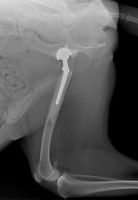

Une prothèse totale de hanche se compose d’une tête fémorale artificielle, en alliage titane ou chrome-cobalt, fixée dans le fémur, et d’une cotyle en polyéthylène. Elle recrée l’articulation atteinte.

Elle est posée chirurgicalement au cours d’une intervention durant en moyenne entre 75 et 90 minutes. Elle demande ensuite une lourde rééducation sur une période allant de 3 à 6 mois. A l’issue de cette dernière, le chien doit normalement avoir retrouvé toute sa motricité, et les douleurs avoir disparu.

On estime à plus de 95% le taux de réussite de la pose de prothèse de hanche pour chien. Les complications qui ont été constatées concernent des infections, des luxations de la hanche et des fractures du fémur ou de la cotyle.